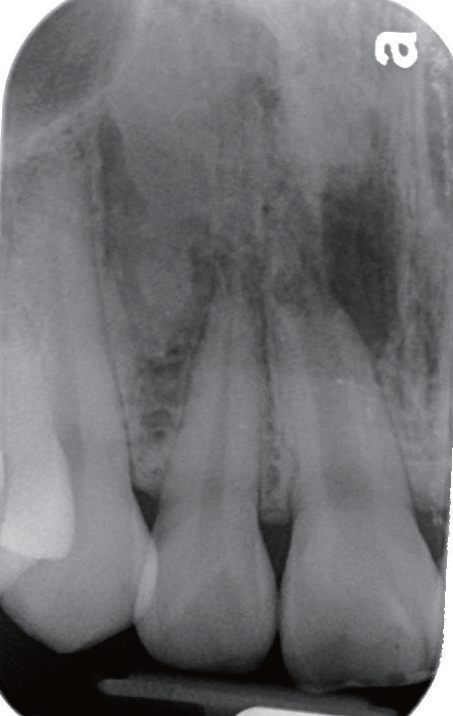

影像学检查   X线片显示11根尖尚未闭合(或根尖已经吸收),且根管宽大,可见根尖有一约8×10 mm的放射性阴影,周边牙槽骨明显缺损。询问患者自述曾经摔倒过,11受到撞击,不记得具体细节。

诊断与治疗计划   对比11 和12(图2)以及11和21(图3),11 的牙根长度较短,其根尖已出现阴影,按正常发育,11的根管应该不会如此宽大。因而推测患者在7~8 岁时,11应该曾经受到强烈撞击,导致牙髓坏死,使得根管没有继续钙化沉积,造成如今管壁相对较为单薄、根尖仍未完全闭合的情形。因而建议可在不给予局部麻醉下进行11开髓,进一步检查根管内部牙髓组织的实际状态。同时借助显微镜辅助进行根管治疗。

图2 对照12,11 根尖未闭合,牙根发育不全,且根尖周出现放射性阴影

牙胶尖什么颜色MTA的临床应用——陈志平教授_https://www.jmylbn.com_新闻资讯_第3张

图3 11 根管过于宽大,管壁略显薄弱,牙根长度较短